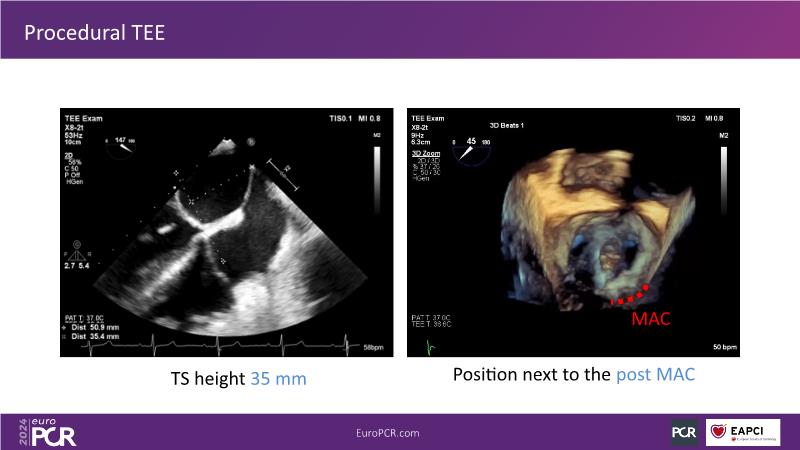

Watch this session to gain insights into the clinical evidence of mitral TEER therapy for the Asian population, learn techniques for implanting a MitraClip in patients with challenging anatomy, and understand how to use the four clip sizes for optimal outcomes. The session also covers educational aspects of clipping in dextrocardia, the benefits of reserve bending of the transseptal needle for tenting and puncture, new steering maneuvers for dextrocardia patients, and the importance of understanding anatomy and collaborating closely with the echo team for success.